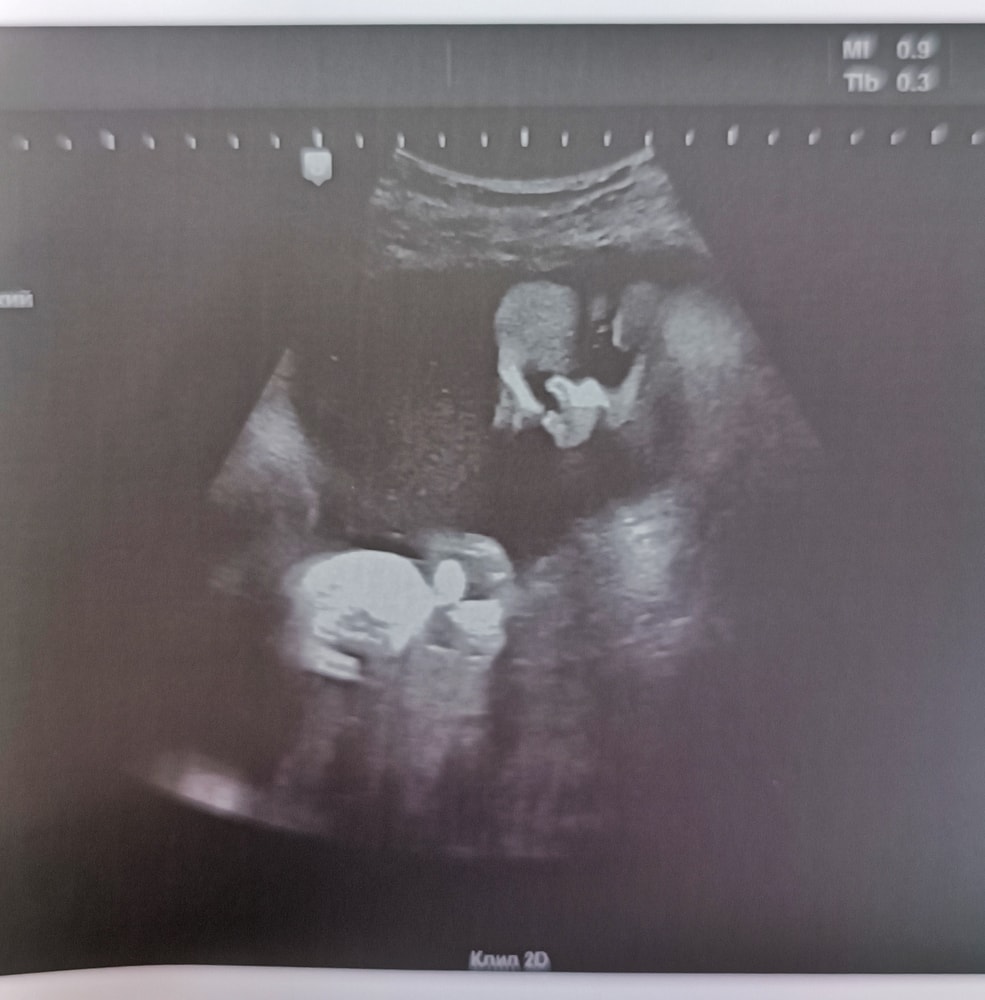

УЗИ 34 недели

Наши будни, наши неделькиВчера ходила на УЗИ, смотрела динамику по весу плода, смотрели количество вод и вообще состояние ребенка.

Сделали НАКОНЕЦ-ТО красивое фото))) было 6 попыток, но все таки удалось)

Вес 2900г🫣 Посчитали, что на пдр будет весить ±4400г. По фотометрии опережает на 2 недели. Также было на УЗИ в 27 недель и на 3 скрининга. Мальчик крупняшка))

Двукратное обвитие конечно... Но сегодня так, завтра 3 обвития, а послезавтра все чисто. В остальном все отлично. Воды в норме, шейка в норме)